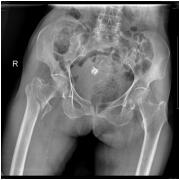

我院骨科繼2016年5月16日成功地為一名平海鎮(zhèn)平海村101歲老人施行右髖部骨科手術(shù)后……

近日我院骨科成功開(kāi)展首例在肩關(guān)節(jié)鏡下單Endobutton治療肩鎖關(guān)節(jié)脫位手術(shù)獲得成功……